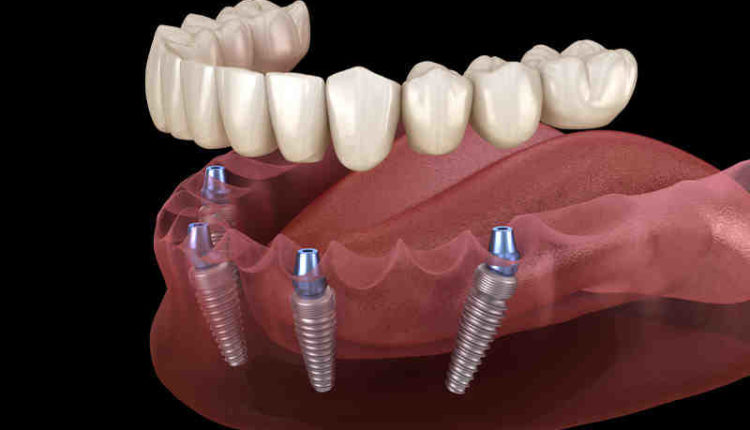

What year did they start doing dental implants?

The first dental implant was installed in a person’s jaw in the year 1965, but did you know that this approach has been around for 4,000 years? Find out how it all started with today’s most popular dental restoration!

How old is dental implant technology? November 23, 2020. Technology in the cosmetic dental industry has come a long way. Dental implants were first invented in 1965, and centuries earlier, elements such as copper or even wood were molded into pegs and used as replacements for teeth.

Who did the first dental implants?

Branemark places the first dental implant. After additional years of research, Dr. Branemark placed the first successful two-stage titanium dental implant in a living patient. This implant took six months to properly integrate into the bone tissue and lasted an astonishing 40 years.

Implants in Antiquity Implants date back to 4,000 years ago, when bamboo pegs were carved in China and used to replace missing teeth. These were fixed to the bone in the mouth.